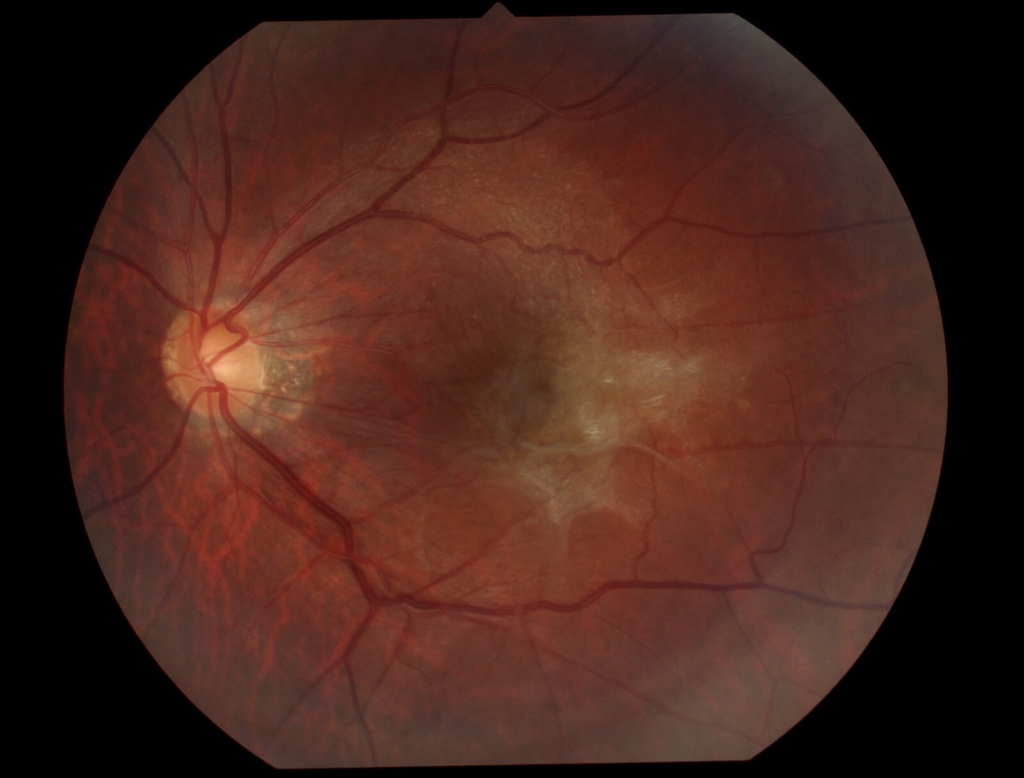

黄斑耳側の網膜表面に膜組織による高反射がみられ、血管が蛇行し偏位がみられる。